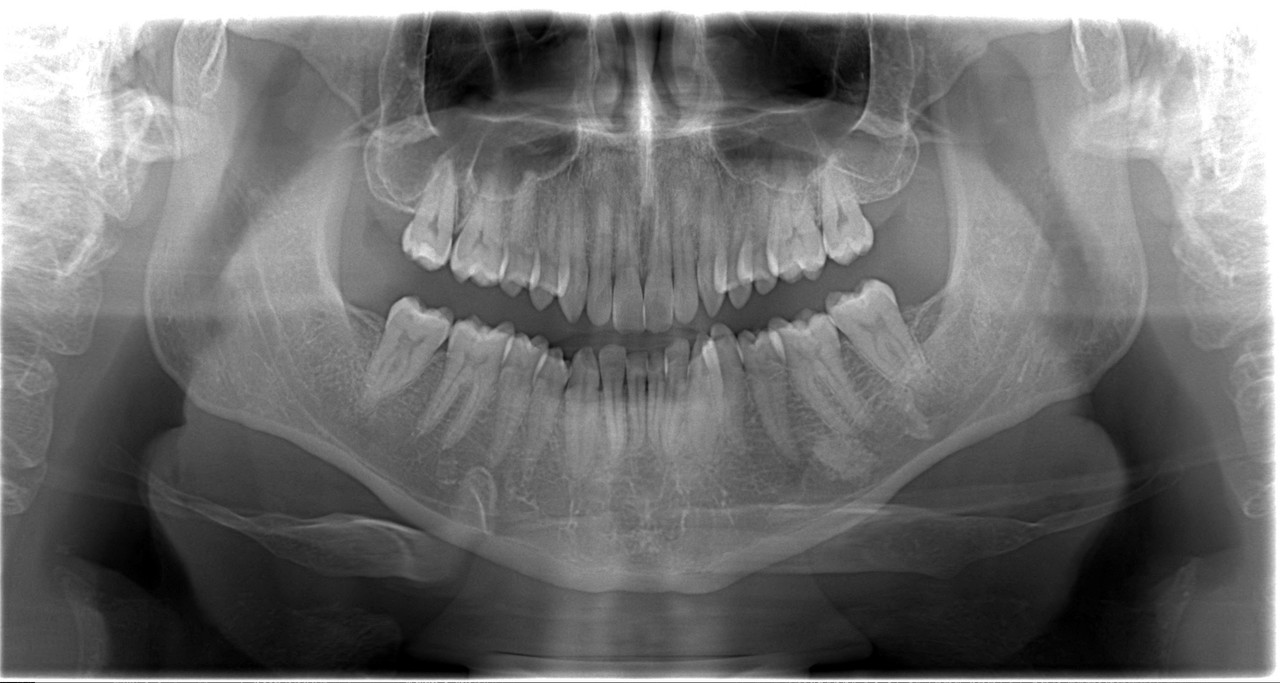

Ik heb de foto bij de tandarts opgevraagd. Wat vinden jullie?[/img]https://i.postimg.cc/8Pg5bcfR/064020-001-20241115.jpg[/img]

[img]https://i.postimg.cc/XvBShKTp/Visi-Quickv12-10-11-2024-1.jpg[/img]

[img]https://i.postimg.cc/XqQzXXTR/Visi-Quickv11-10-11-2024-1.jpg[/img]